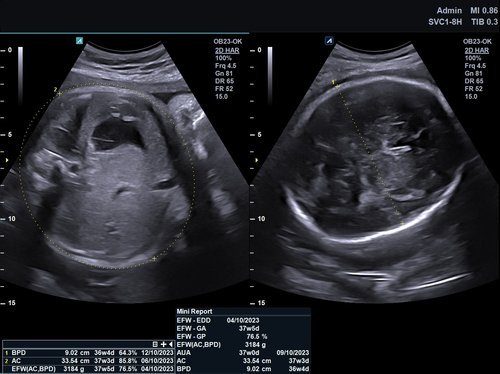

• SVC1-8H (1-8 MHz) für Ultraschalluntersuchungen in Bereichen Abdomen, Geburtshilfe, Gynäkologie, Urologie, Pädiatrie, EM